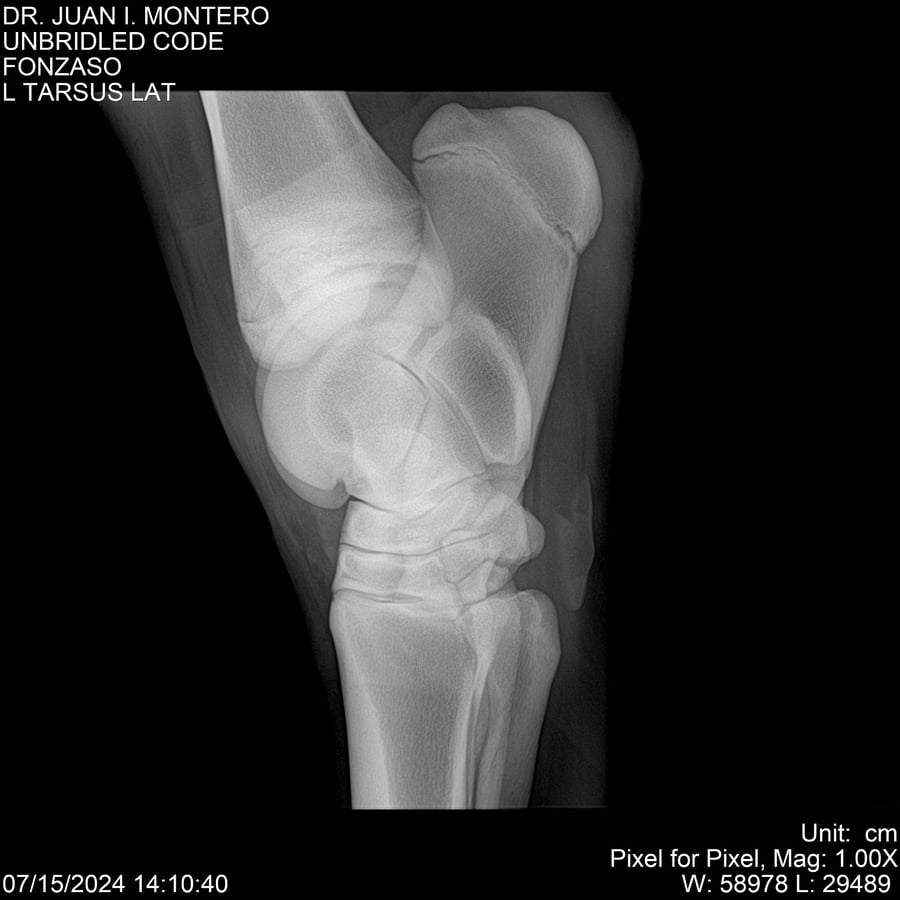

• Empresa: Abelenda N. R., Walter Hugo